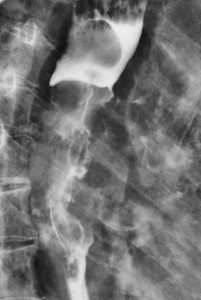

Метастазы в легких — фото рентгенограммы. Округлые тени — метастазы рака пищевода. Хорошо виден большой узел округлой формы вблизи переднего отрезка 2-го ребра. На снимке справа - циркулярное сужение пищевода за счет опухолевого утолщения его слизистой оболочки.

Как выглядят метастазы в легких на рентгене? Слева — узловые образования у пациента с раком яичка. Справа - метастазы рака яичников гематогенного характера с выраженным опухолевым лимфангиитом (обратите внимание на деформированный сетчатый, линейный характер легочного рисунка).